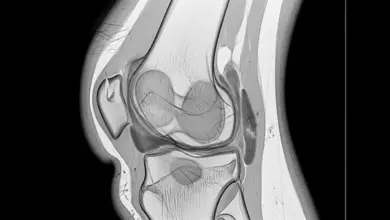

Na reconstrução do LCA, o cirurgião cria túneis no fêmur e na tíbia para posicionar o enxerto no trajeto anatômico do ligamento original.

O parafuso pode ser colocado nesses túneis para manter o enxerto estável.

Isso explica por que muitos pacientes visualizam o material no raio X após a cirurgia. O implante está no osso, fazendo parte da fixação planejada durante o procedimento.

Vale destacar um ponto importante: ele não fica solto dentro da articulação.